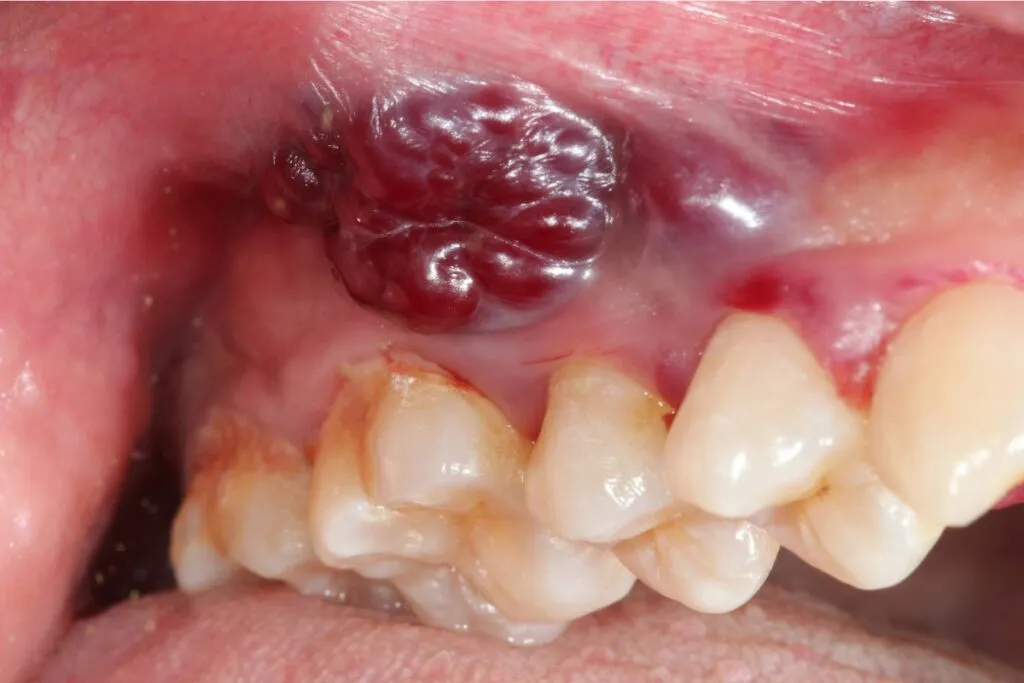

Guzki, zgrubienia i stwardnienia: jak je rozpoznać dotykiem?

Należy zwrócić uwagę na wszelkie wyczuwalne pod palcami guzki, zgrubienia lub stwardnienia w obrębie warg, języka, dziąseł lub wewnętrznej strony policzków. Zmiany te mogą być początkowo niewielkie i nie dawać żadnych dolegliwości bólowych, dlatego ważne jest regularne badanie jamy ustnej palpacyjnie.